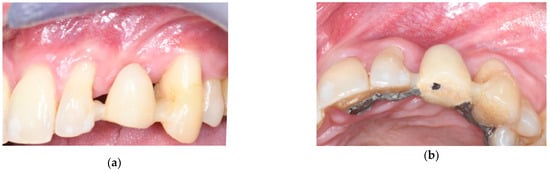

2. Connective Tissue Substitutes: Properties and Applications

3.1. Soft Tissue Augmentation Before Implant Installation

3.2. Soft Tissue Augmentation During Implant Installation

3.3. Soft Tissue Augmentation After Implant Installation